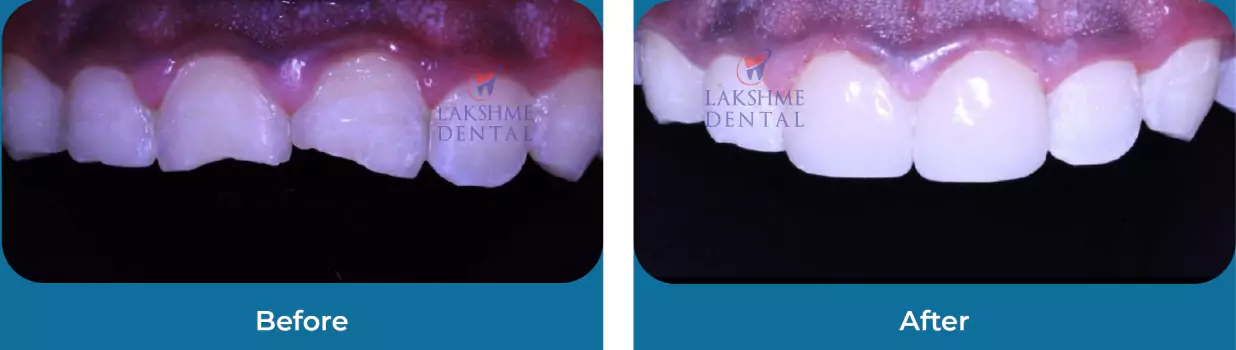

Discoloured Teeth

Esthetics

Broken Teeth